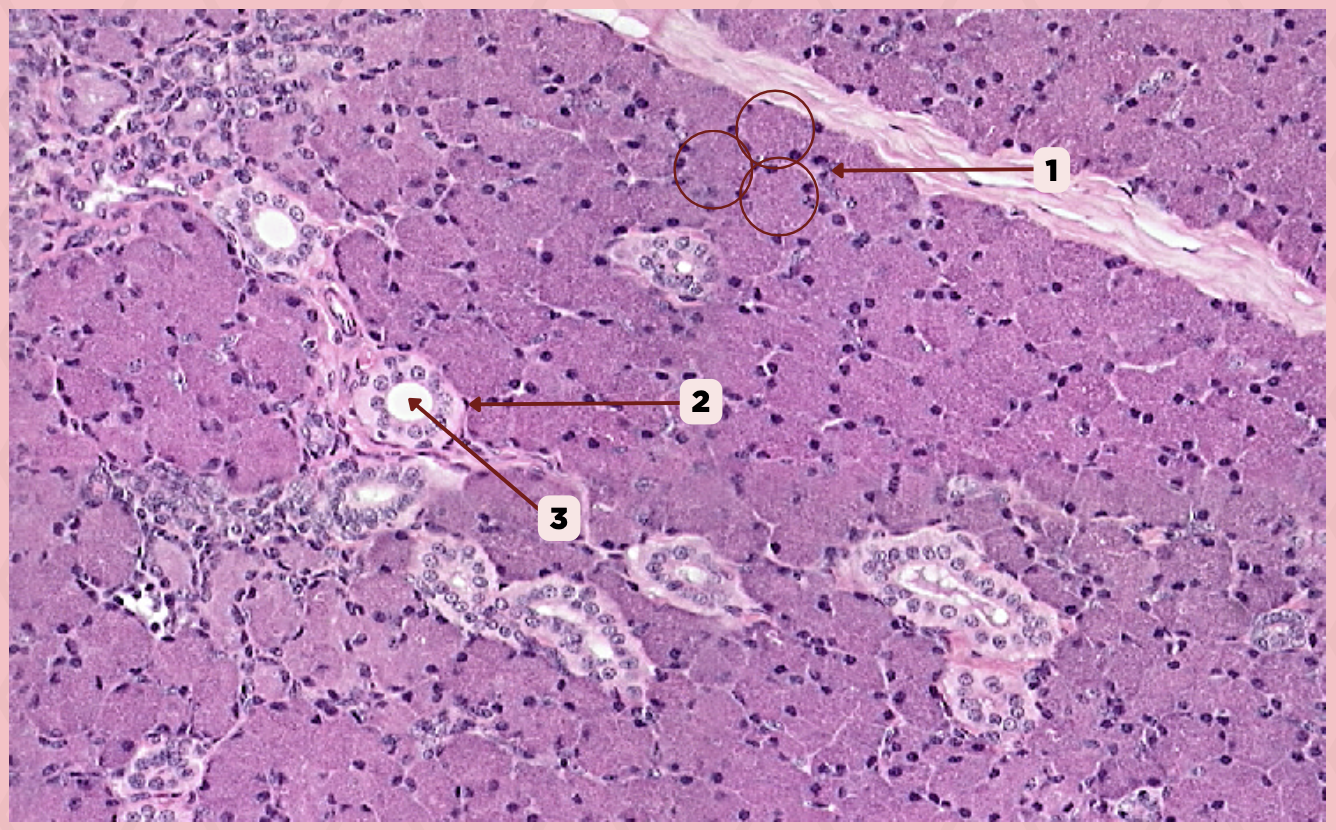

Parotid

Identify the specimen.

Secretory Acini

Identify the structure labeled as 1.

Myoepithelial Cell

Identify the structure labeled as 2.

Secretory Duct

Identify the structure labeled as 3.

Parotid

Identify the specimen.

Capsule

Identify the structure labeled as 1.

Lobule

Identify the structure labeled as 2.

Lobe

Identify the structure labeled as 3.

Connective Tissue

Identify the structure labeled as 4.

Parotid

Identify the specimen.

Adipocyte

Identify the structure labeled as 1.

Connective Tissue

Identify the structure labeled as 2.

Intercalated Duct

Identify the structure labeled as 3.

Striated Duct

Identify the structure labeled as 4.

Serous Gland

Identify the structure labeled as 5.